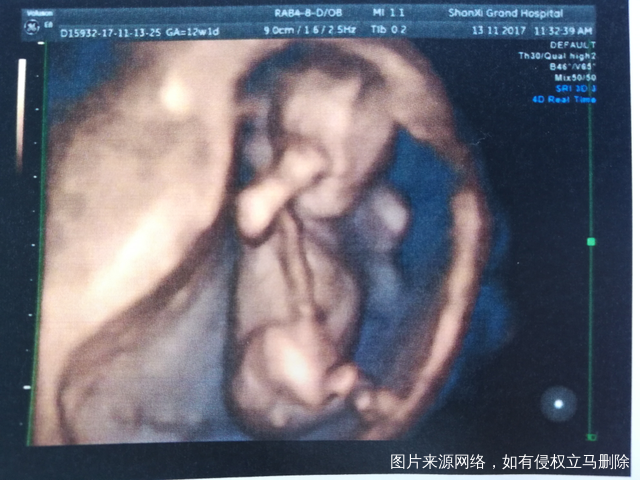

谁会看男孩女孩,来帮我看看